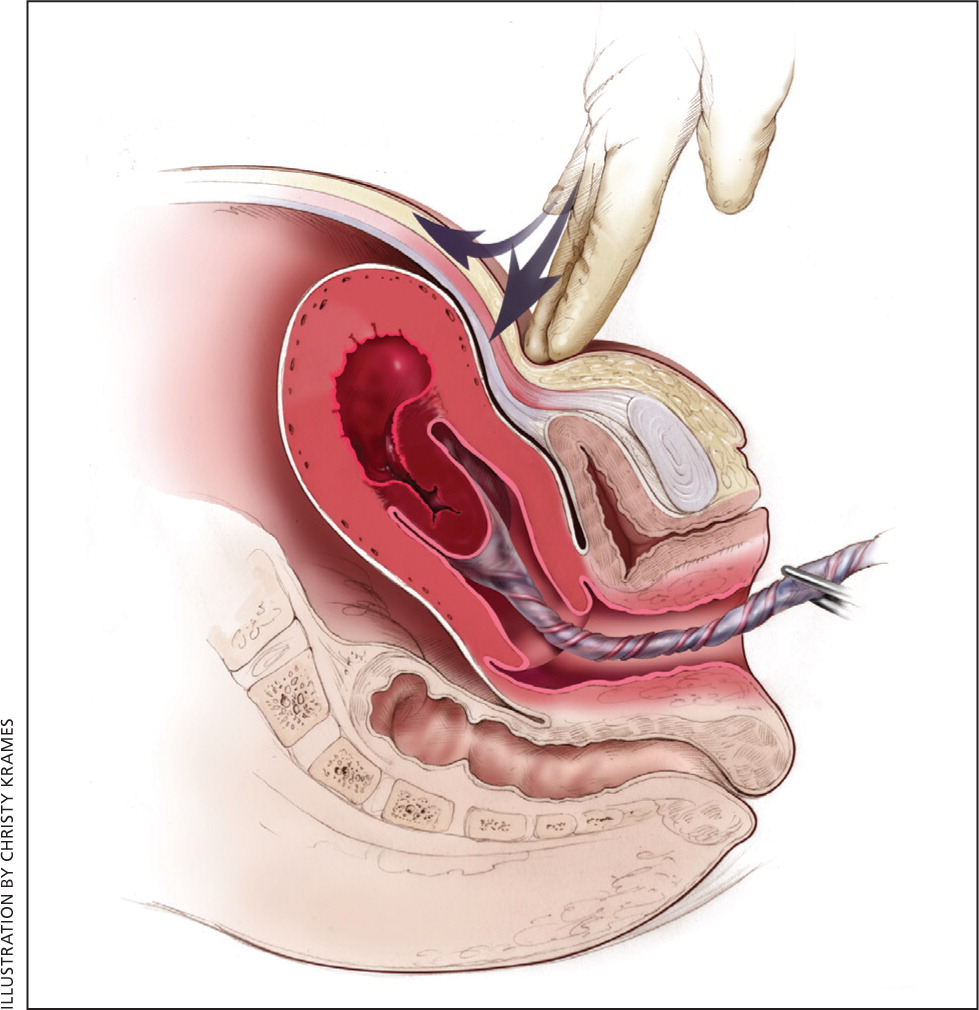

Медицинская визуализация: Признак Кюстнера-Чукалова